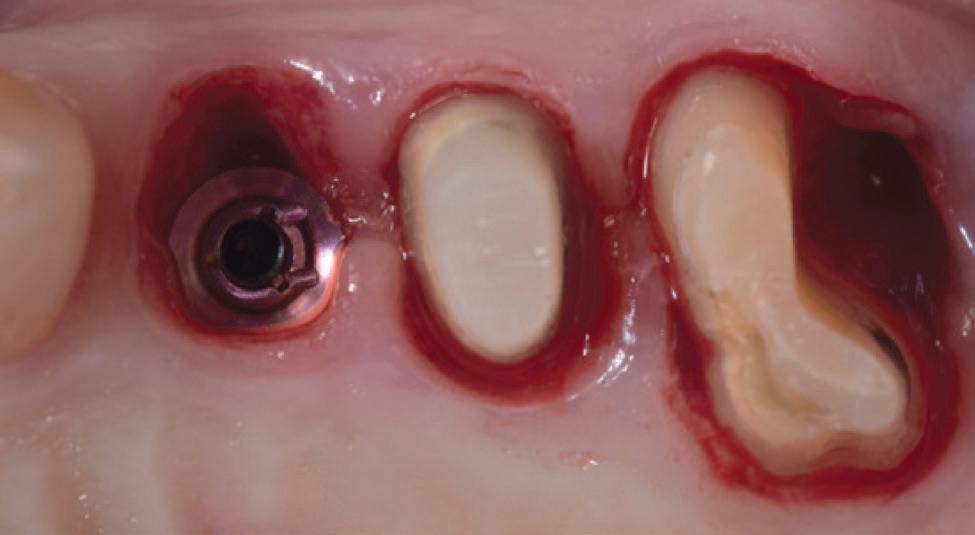

In its continuing commitment to reimagine and improve solutions for the dental industry, Carestream Dental has launched the Advance Edition of the CS 8200 3D, along with the latest updates in automated implant planning. The CS 8200 3D Advance Edition is the newest addition to the CS 8200 3D Family and builds on the success of its award-winning predecessors with extended fields of view—including two new larger FOVs—and AI-powered software that streamlines and automates the implant planning workflow.*

• AI-powered implant planning:* The enhanced implant planning module automates the implant workflow, allowing practitioners to plan implants faster and with greater precision.

Additionally, new AI-assisted software accelerates the entire implant planning process by automating time-consuming tasks. Now, preparing data for implant cases— like merging CBCT volumes with digital impressions—designing virtual crowns and digitally placing implants is all handled automatically, making implant planning faster and easier. When combined with a prosthetic-driven approach, these software updates improve treatment predictability and give doctors the confidence to deliver precise and successful implant outcomes.